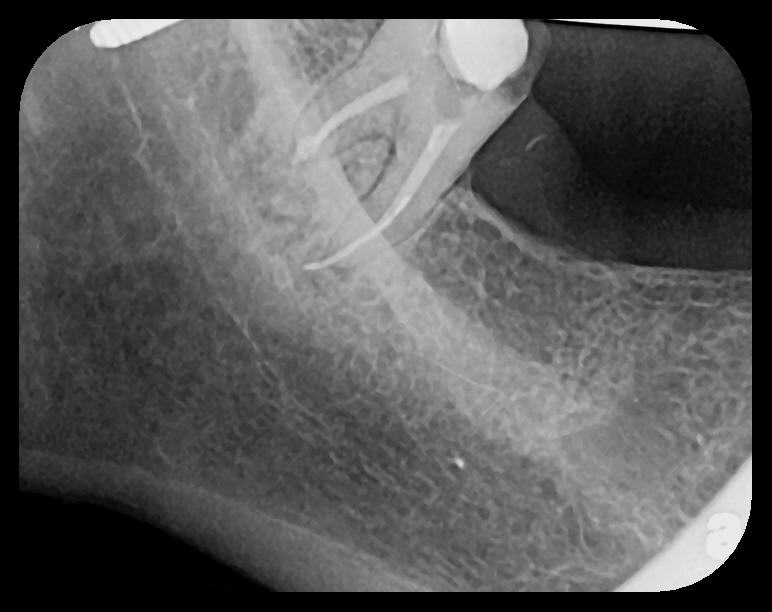

There are two specific types of DIDR sensor systems available to dentists in the marketplace: the hard-wired (HW) sensor and the photostimulable phosphor (PSP) sensor,1,2 also commonly known as phosphor "plates." A desirable feature common to both modalities is the ability to expose either bitewing (BW) or PA radiographic images. The BW radiograph (Figure 1) is usually considered more appropriate for caries detection, whereas the PA (Figure 2) is diagnostic for several different anatomic and pathologic issues.7

Fig 2. Left: PSP vertical PA radiograph of

maxillary bicuspid area demonstrating full root structure, several millimeters of bony anatomy beyond apices and maxillary sinus. Tooth No. 4 may be

traumatized as periodontal ligament is widened. Right: PSP horizontal PA radiograph of maxillary bicuspid area. Tooth No. 12 shows widened apical

periodontal ligament presumably caused by deep restorative filling. Some loss of supporting bone is evident interproximally, especially pronounced

between tooth Nos. 14 and 15.

Figure 2